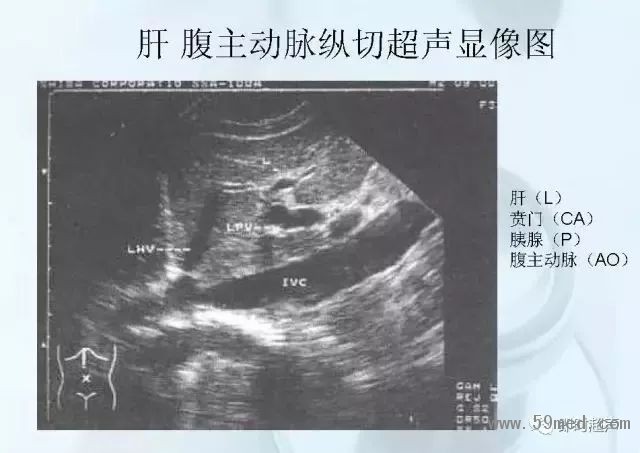

新聞中心 收藏!正常B超解剖圖譜,超實用!